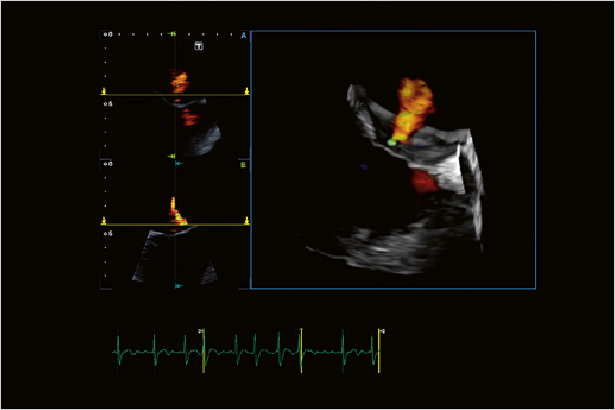

在Aplio i900上可以看到精細和清晰的彩色多普勒血流成像。優異的敏感性和分辨率能夠提供更多臨床信息。

心臟實時3D成像讓Aplio i900可以對心臟的四個房室進行成像和定量。